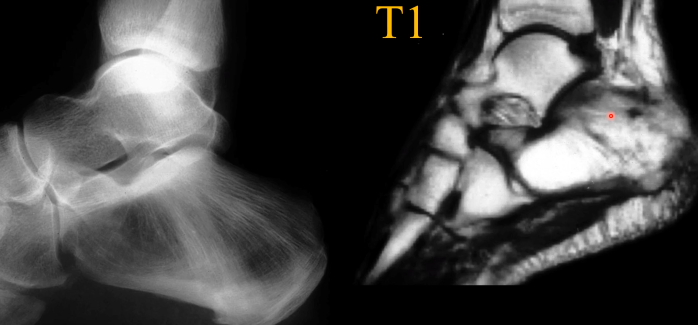

Bowing

Fractures

- Fractures Complètes et incomplètes

- Banana Fractures

vertèbres en cadre image Blade of Grass / Brin d’herbe / Candle Flame Signbanane enOstéodystrophie déformante osseux osteodytrophie